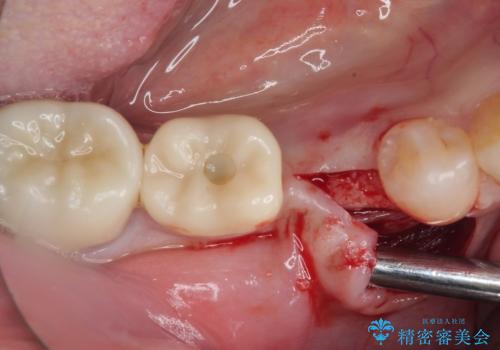

状況次第では抜歯が必要となり、その際にはインプラント治療を行うことを了承いただいた上で、破折していない場合には根管治療を行うこととしました。

土台の材料を外して顕微鏡下で確認したところ、歯根にまで及ぶ破折が認められたため、インプラント治療を行うこととしました。

他にも銀歯や欠損となっている歯に対しての治療も希望されたため、補綴治療を行うこととしました。